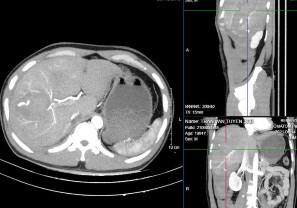

Hình 4.1: CTG độ III, tổn thương dạng đụng dập nhu mô gan HPT VI – VIII trước (T) và sau tiêm thuốc (P).

Nguồn: BN Đặng Mạnh T, 34t Mã HS: 2118010